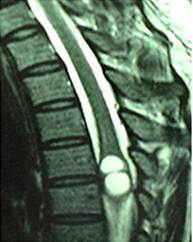

Figure 2

Photomicrographs of the histological specimen showing the cysticercosis cyst wall with neutrophile granulocyte.lymphocyte and necrosis cell. (H&E×100)

The patient underwent laminectomy from T4 to T5, and the spinal cord was found swollen. When a midline myelotomy was performed, a white cystic lesion was seen and clear fluid was then aspirated. The cyst wall of which slightly stuck to the surrounding spinal cord. In order to dissect the cyst with minimal injury to the peripheral tissue, the cystic liquid was partly withdrawn first and the slackened cyst was removed totally. The liquid was yellowish and transparent. Histological examination of the resected sample showed cysticercosis.